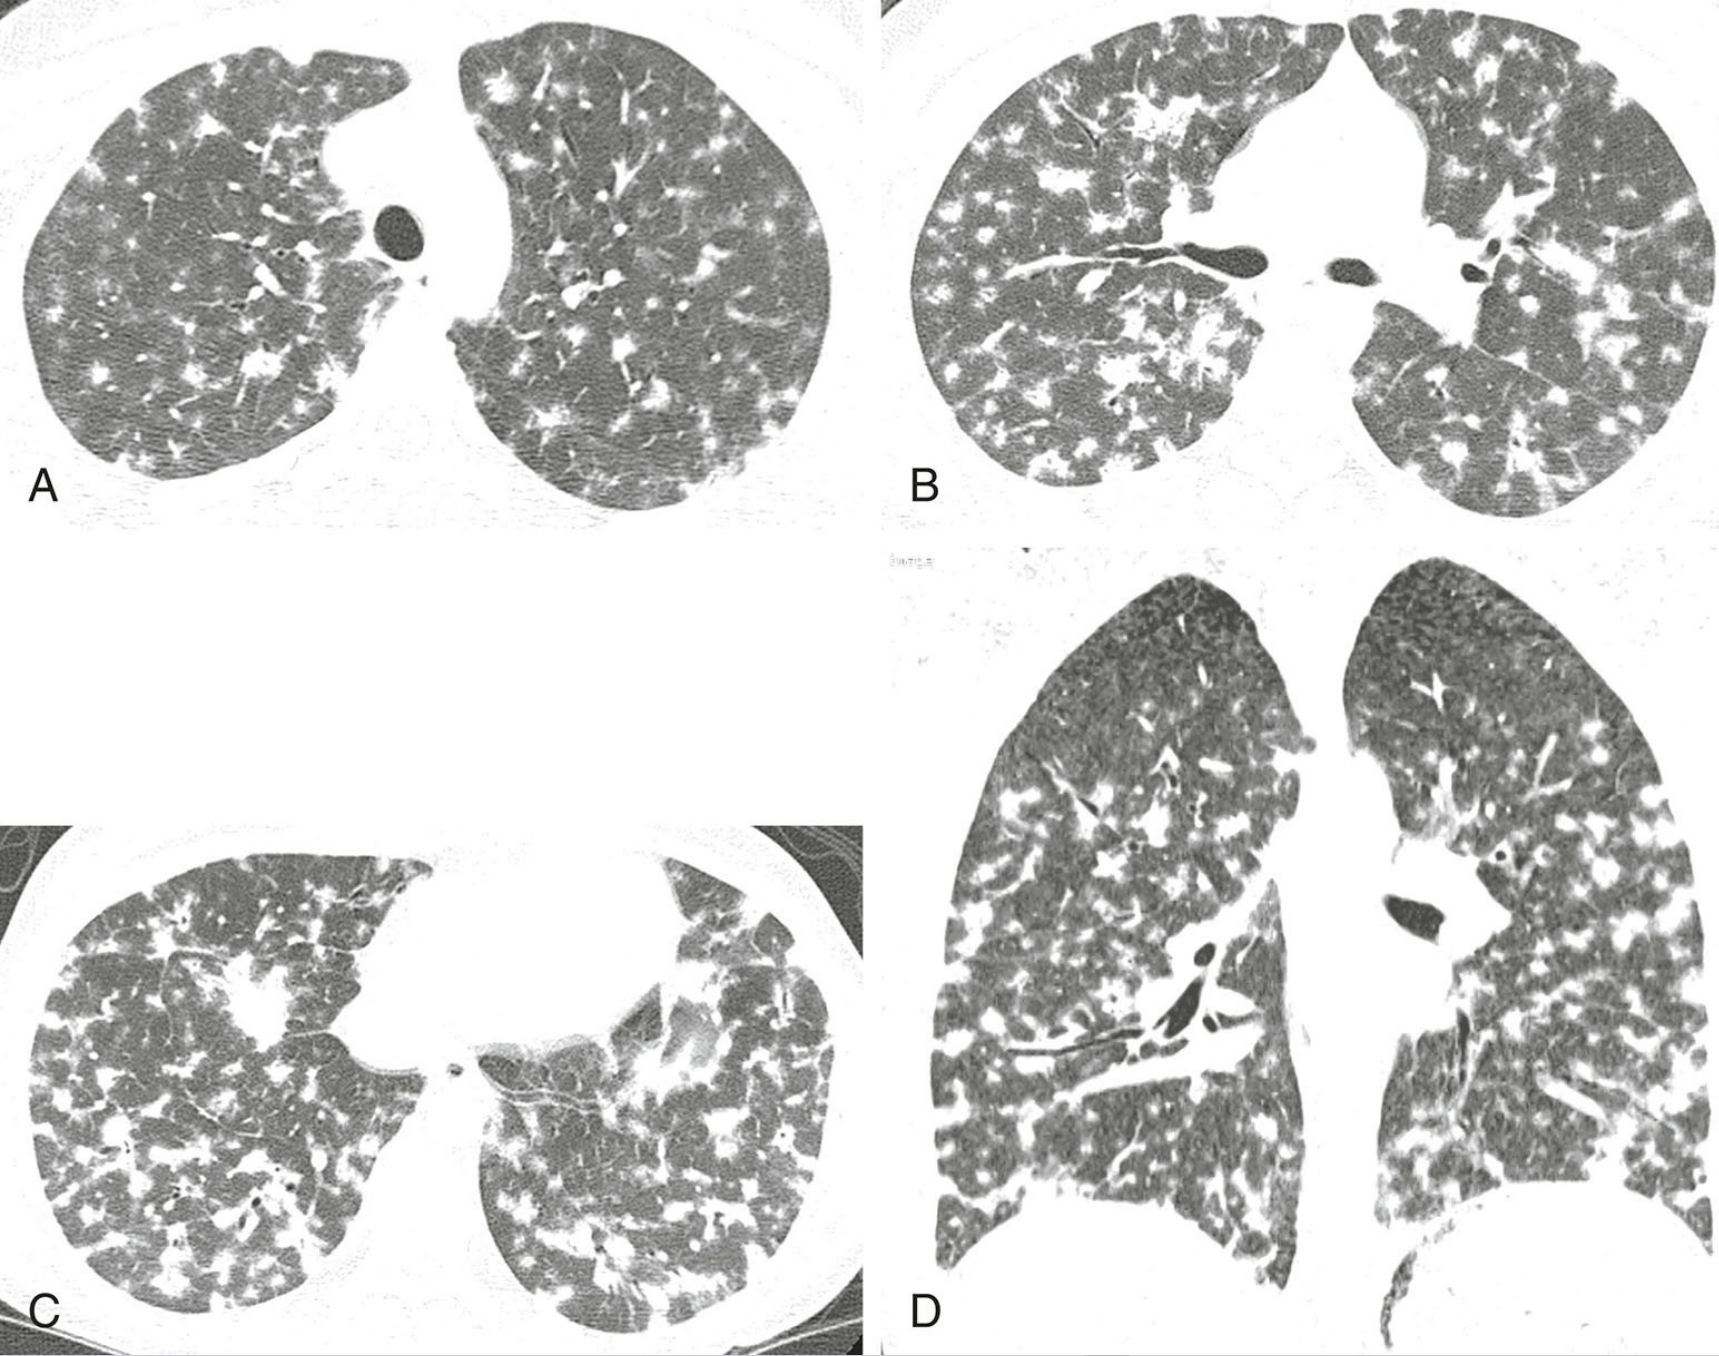

27548bcf9c93bc25a1cd816613e8485a.png

纤维化型非特异性间质性肺炎(NSIP)的典型表现。

4例纤维化型NSIP,每例均显示不规则网状影(蓝箭)和牵拉性支气管扩张(红箭)为主要异常。紧邻胸膜下肺区不受累(A至C)高度提示本病,但有时无此征象(D)。蜂窝征缺如或不明显。